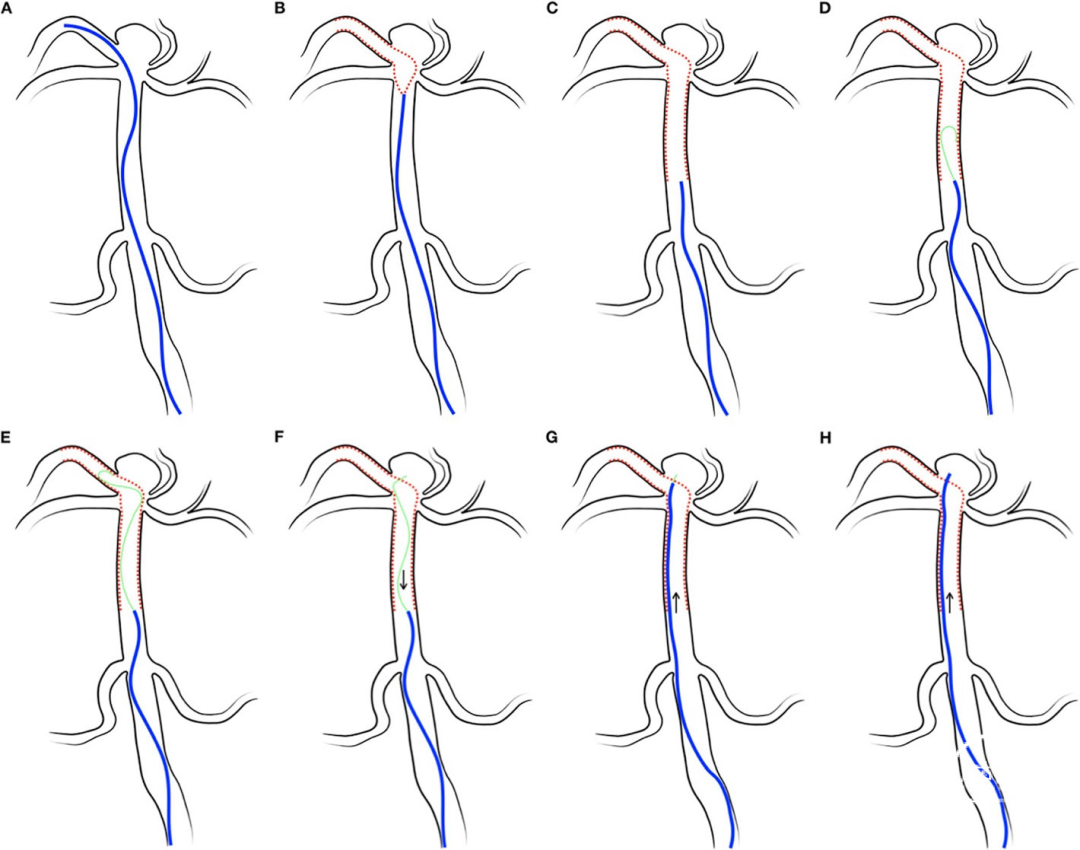

患者年纪大,弓上血管迂曲,血管多发狭窄,宽颈动脉瘤拟使用支架辅助栓塞,计划首先尝试中间导管建立通路, SL-10微导管送至载瘤动脉远端以备输送支架,另外使用SL-10微导管塑形后进入动脉瘤栓塞。

术中评估颈内动脉起始部迂曲,后方血管至动脉瘤通路尚可,遂决定尝试首先SL-10微导管到位释放支架。

微导管顺利到位,若再上微导管担心指引导管过低,支撑力不够,遂释放3.0mm*15mm Atlas支架,后撤SL-10微导管穿网孔栓塞动脉瘤。

术中释放3.0mm*15mm Atlas支架到位后,后撤预塑45°的SL-10微导管,使用微导丝引导轻松穿网孔进入动脉瘤。

Atlas支架可通过SL-10微导管输送,使其可轻松到达血管更远端,且无头端设计,提供灵活操作空间。且在路径迂曲,痉挛狭窄等特殊情况下释放支架与栓塞动脉瘤可使用同一套系统,避免多系统的互相干扰影响。

Atlas支架独特的开环设计和自膨式打开,保持远端开环的节段扩张,准确释放。